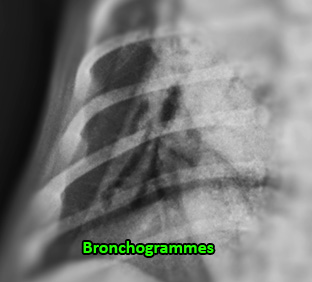

Il s’agissait – comme la majorité d’entres vous le suspectiez – d’un mégaoesophage congénital. L’oesophage (flèches jaunes) est sévèrement dilaté par de la nourriture, déplaçant et comprimant la trachée ventralement. La VD révèle également un patron alvéolaire au lobe moyen droit avec de beaux bronchogrammes aériques (voir image magnifiée), compatible avec une pneumonie par aspiration (fausse déglutition). Pourquoi ce patron n’est pas reconnu sur la latérale ? Simplement parce qu’il s’agissait d’une latérale droite qui force le poumon droit à s’affaisser au profit du poumon gauche, limitant ainsi le contraste radiographique nécessaire à la distinction de cette pathologie. On remarque aussi sur la VD la silhouette du thymus formant un signe de « voile » s’étendant vers la gauche.